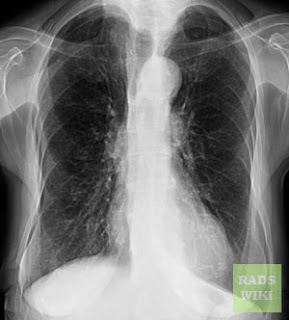

- Tuberculosis paru

- Infeksi bakteri berat (pneumonia)

- Pneumonia pneumocystis carinii